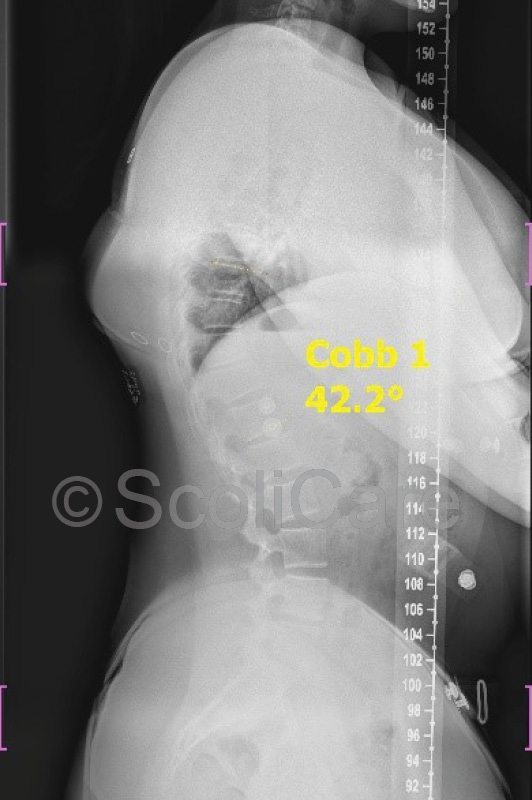

In-brace x-rays were taken one month after the brace fitting which indicated that the curve could be reduced from 67° down to 42° whilst wearing the brace (Figure 2).